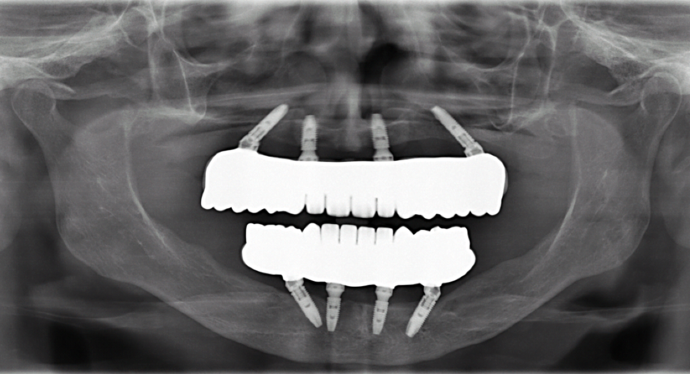

All-on-4/ Full Mouth Dental Implants / Teeth in a Day: Case 12-HM-Upper and lower All-on-4 bridges

This healthcare professional unfortunately had gum disease early on in her life and was given a top denture and was unhappy with her lower partial. She was trying to hold on to the very last tooth to avoid wearing a lower denture. She had consulted many doctors who told her that she had no bone for dental implants and would need major bone grafting procedures. Dr. Bidra identified areas of available bone using a CT scan, and successfully performed the All on 4 procedure on upper and lower (top and bottom) without the need for any bone grafting, and gave her fixed permanent zirconia bridges.

Procedures : extractions, implants, All on 4 , Teeth in a day, no bone grafting and full mouth reconstruction with monolithic zirconia bridges.